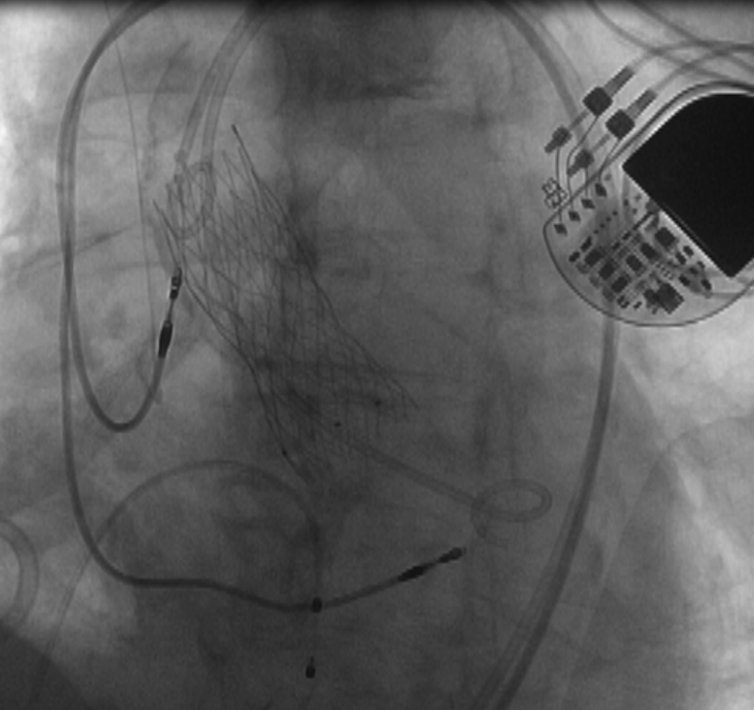

在与患者家属充分沟通并取得理解和同意后,郭延松教授带领团队联合重症医学科、麻醉科、超声科、放射科、心血管外科、手术室等多学科对手术策略及围手术期可能出现风险所制定的预案进行反复研究讨论后,决定为患者选择经皮导管主动脉瓣置入术+经皮冠脉内支架植入术,解除主动脉瓣重度狭窄,打通心脏血管的阻塞,恢复患者正常的血液循环和血流动力学,经过团队的精心操作,成功为患者修复主动脉。

术后经重症监护室及心内三科医护人员的精心调理和治疗,患者上述不适均缓解,上述系统器官功能得到明显改善,顺利出院。

经皮导管主动瓣置入术

该术式是目前治疗主动脉疾病的先进诊疗技术,无需开胸,仅需通过股动脉6mm穿刺点即可完成主动脉瓣置换,恢复瓣膜原有的正常开闭功能,极大改善患者的生活质量。我院自开展经皮导管主动脉瓣置入术以来,通过多学科团队合作已成功为众多主动脉瓣重度狭窄患者实施经皮导管主动脉瓣置入术治疗,其中80岁以上患者占比近三分之一,90岁及以上患者共5位,目前手术例数及操作水平居全国前列,为心脏瓣膜病患者带来福音。